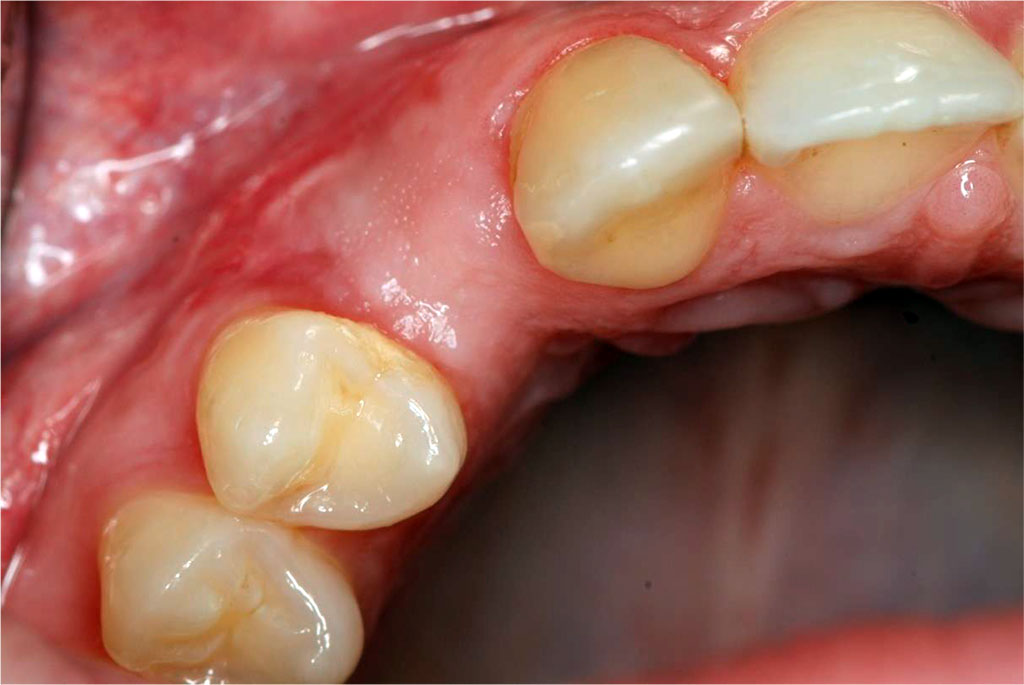

The patient, aged 42 was reffered from another dental office for peri-implant soft tissue augmentation in the aesthetic zone of the maxilla in the area of the implant located in position 13. Her history included type 2 diabetes, pharmacologically stabilised (she was taking Metformin 750mg twice a day), and no known allergies. Family history, no genetic burden. On extraoral clinical examination, no apparent facial asymmetry, chin and submandibular group A lymph nodes not palpable, not painful. Trigeminal nerve outlets not painful. No pathology in the temporomandibular joint. Intraoral clinical examination revealed a thin gingival biotype and a insufficient transverse gingival dimension in the vicinity of the implant at the crown neck of tooth 13, with no signs of inflammation, bleeding, bacterial plaque or pathological depths at the 6 points examined around the implant (Fig.1). The thickness of the keratinised gingiva at the implant at position 13 was measured by ultrasonography. The thickness of the keratinised gingiva was 0.75 mm (Tab.1). The width of the keratinized gingiva in the specified area was 1 mm (Tab.1).

Fig.1 The condition of the peri-implant soft tissues before sCTG augmentation.